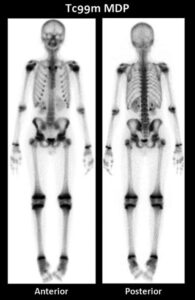

Tra queste, la scintigrafia ossea con traccianti come il Tecnezio-99m MDP rimane la tecnica di screening più diffusa, pratica ed economica per ottenere una valutazione completa di tutto lo scheletro. La sua elevata sensibilità la rende uno strumento eccellente per la rilevazione precoce della malattia.

L’aspetto più caratteristico delle metastasi ossee in scintigrafia è quello di numerosi focolai di captazione aumentata del radiofarmaco, distribuiti in modo casuale e predominanti nello scheletro assiale (colonna, bacino, coste e cintura scapolare).

Questa distribuzione riflette l’elevata vascolarizzazione e attività metabolica del midollo osseo in queste sedi. Le metastasi alle ossa periferiche degli arti sono, invece, un evento più raro.

Pattern diffuso (Super-scan): in stadi metastatici molto avanzati, l’intero scheletro assiale può essere coinvolto da un carico tumorale massiccio.

L’immagine risultante, detta “superscan“, mostra un’intensa e uniforme captazione del radiofarmaco in tutte le ossa.

È cruciale distinguere questo pattern da quello causato da malattie metaboliche dell’osso, come l’iperparatiroidismo.

La differenza principale risiede nella distribuzione: mentre il super-scan da metastasi è confinato allo scheletro assiale, le malattie metaboliche mostrano un coinvolgimento anche del cranio, della mandibola e delle diafisi delle ossa lunghe.